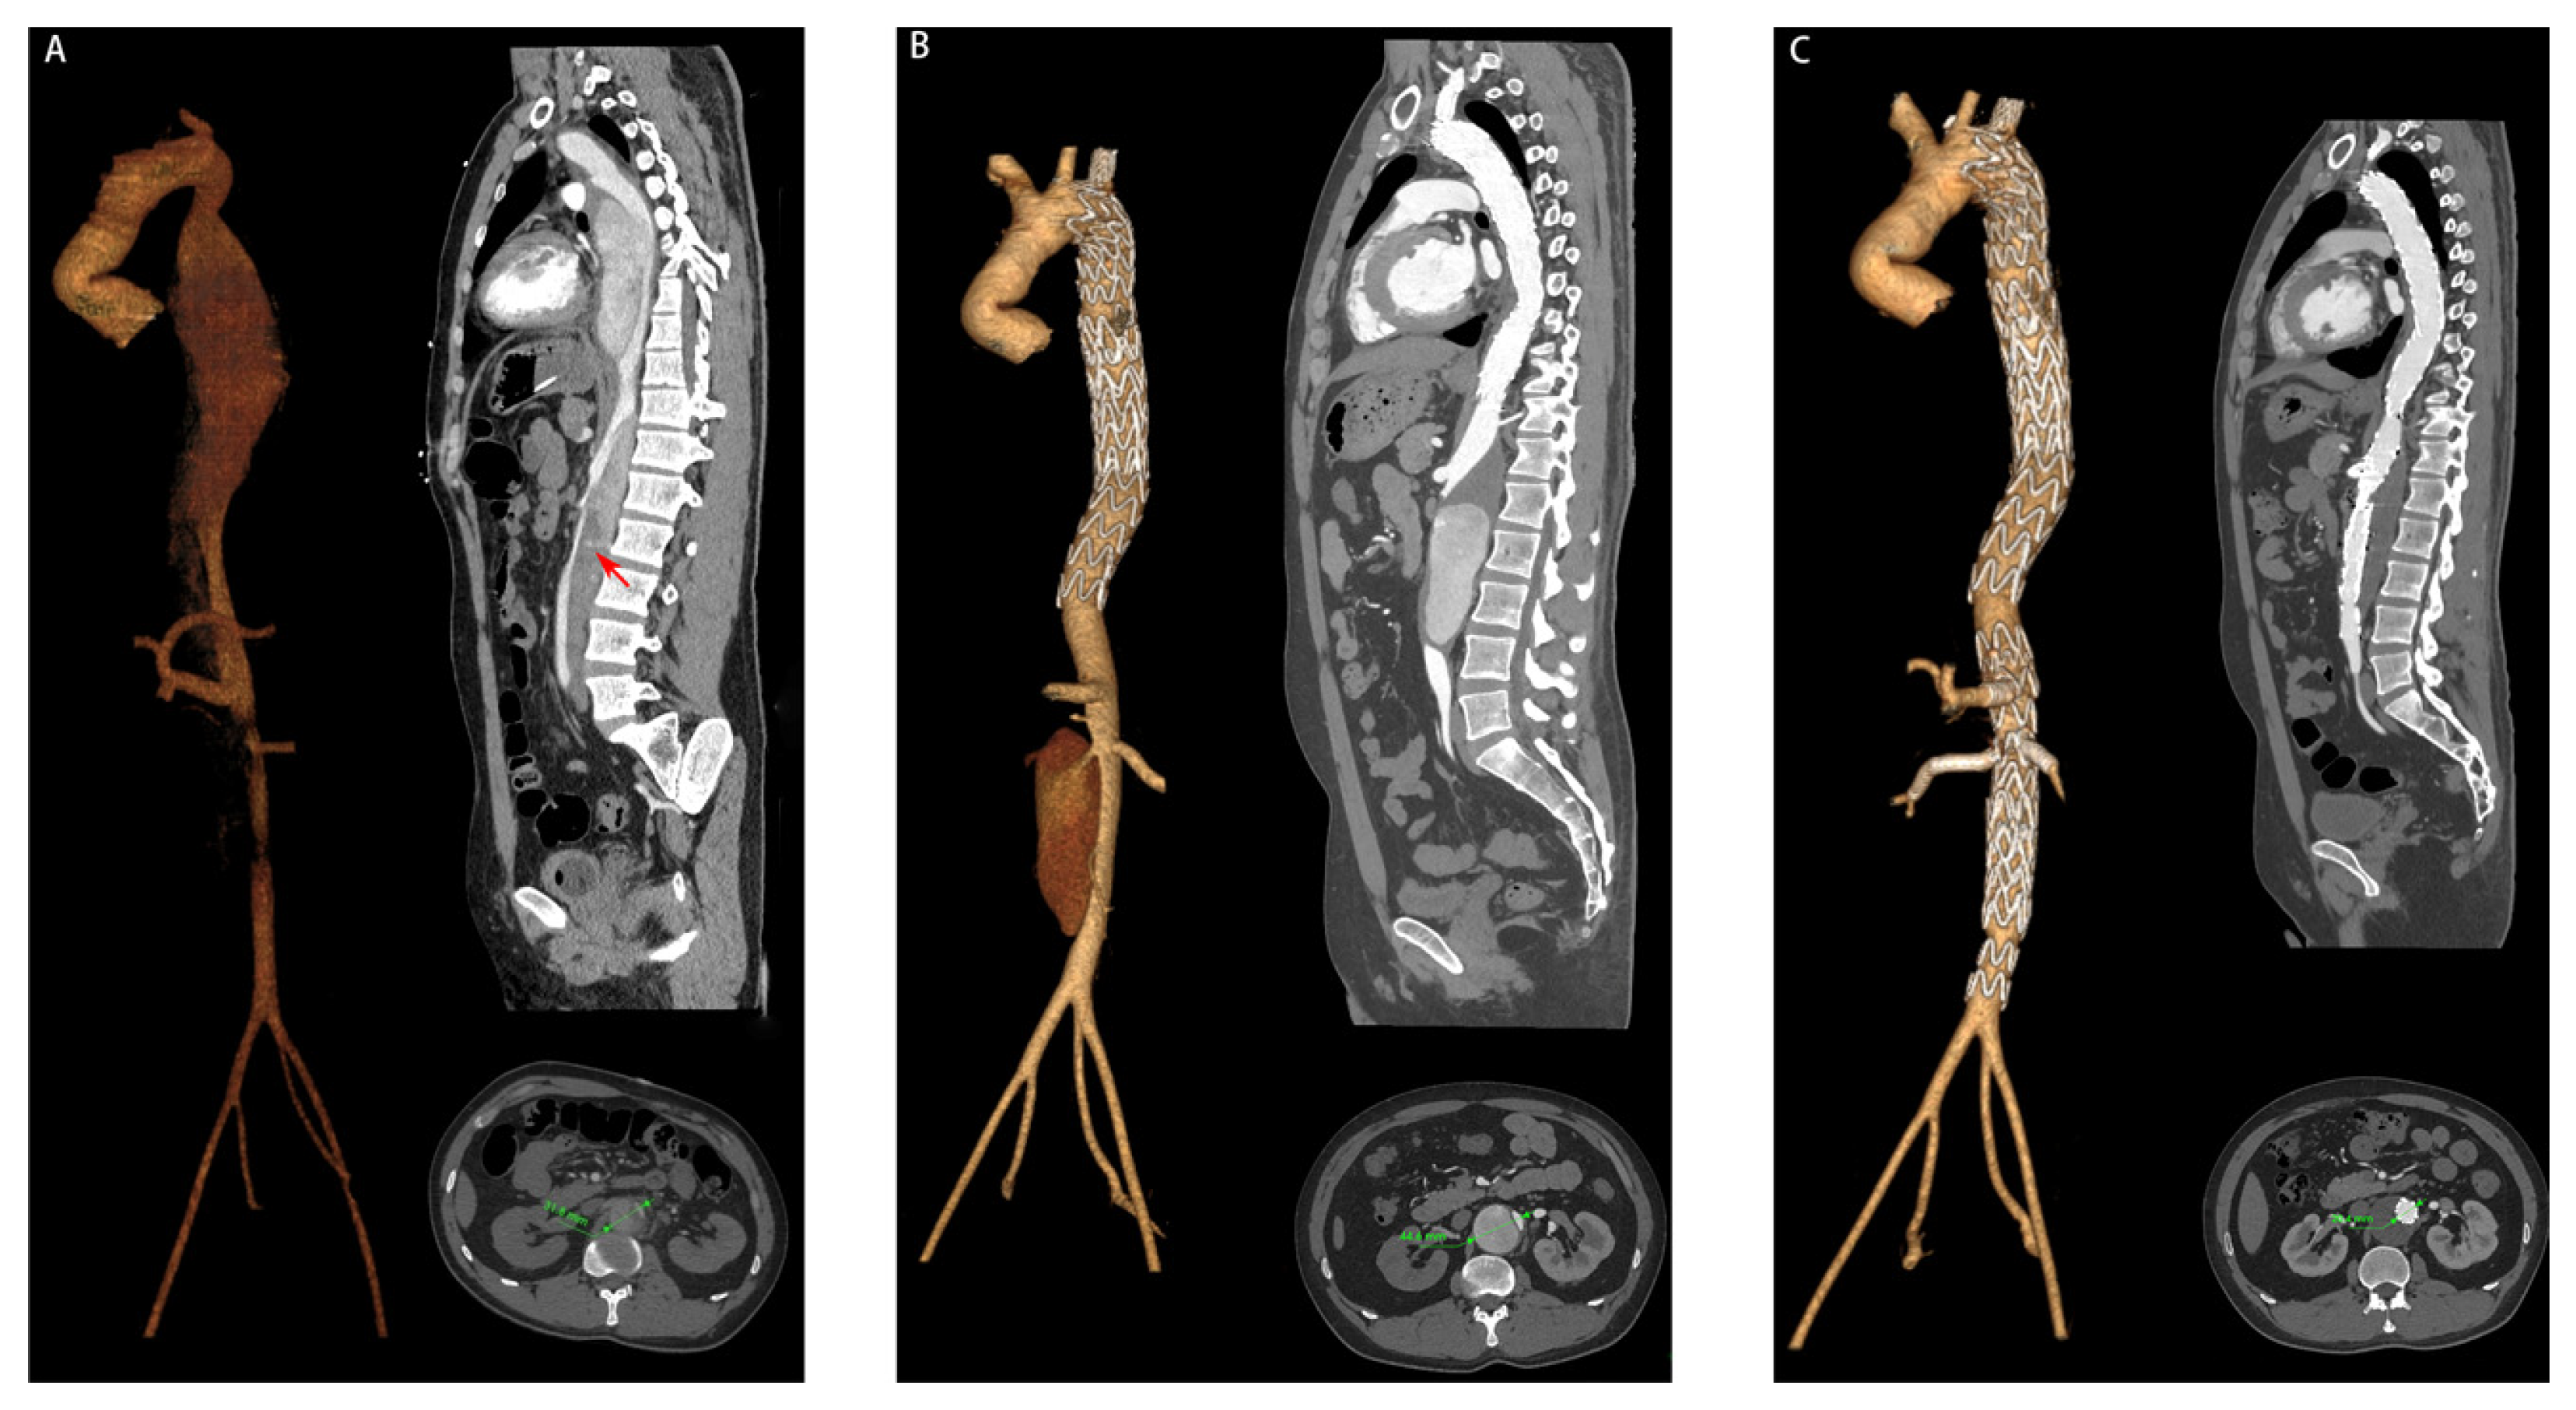

| Partial thrombosis of FL, n (%) | 9 (60.0) | 7 (8.6) | <0.001 |

| Maximum descending aortic diameter (mm), mean ± SD | 41.3 ± 4.5 | 37.5 ± 3.0 | <0.001 |

| T10 | Expanded group | 40.1 ± 4.2 | 44.0 ± 4.0 |

| Non-expanded group | 36.3 ± 3.8 | 36.1 ± 4.4 | |

| T12 | Expanded group | 35.8 ± 3.7 | 40.6 ± 5.3 |

| Non-expanded group | 34.4 ± 2.8 | 35.1 ± 3.2 | |

| L2 | Expanded group | 30.0 ± 3.3 | 32.5 ± 2.7 |

| Non-expanded group | 28.8 ± 2.4 | 29.3 ± 2.4 | |

| L4 | Expanded group | 27.5 ± 2.9 | 28.7 ± 3.0 |

| Non-expanded group | 24.2 ± 2.5 | 24.7 ± 2.7 |